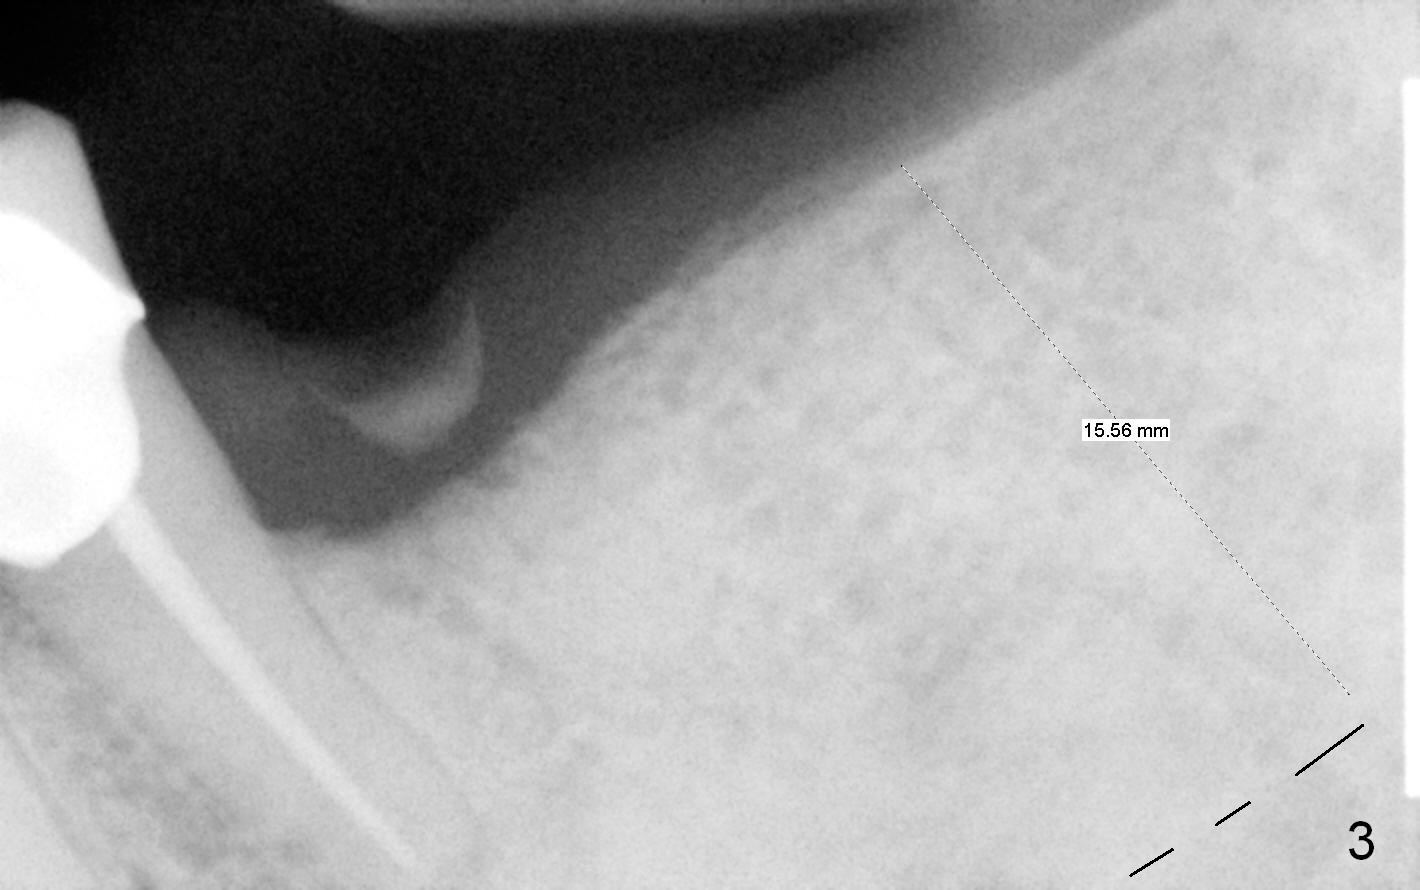

After cementation of crown at #3 and implant placement at #6, the 70-year-old lady will return for #18 and 20 implant placement and possible an immediate provisional (fixed partial denture) FPD (Fig.1,2). Before incision, start osteotomy 5 mm distal to a surgical stent (with #19 as the most distal tooth) and at #18. After incision, the initial bone depth is 11 mm (Fig.3) and insert parallel pins with depth marks for PA. If there is enough bone and bone density is low, extend the depth to 14 mm. Tatum tapered implants are going to be used. Which set of drills should be opened? Set speed at 50 RPM. Fig.3 is long horizontally. It should have been taken with #1 sensor. Beside, she is skinny. The dental arches are narrow.